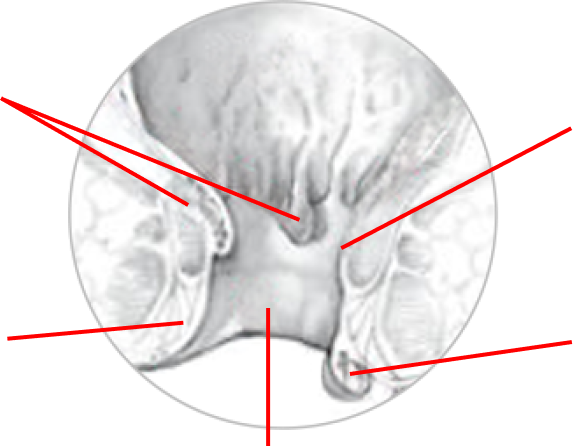

Hemoroidy

HEMOROIDY

Hemoroidy wewnętrzne

Żyły

Żyły

Hemoroid zewnętrzne

Kanał odbytu